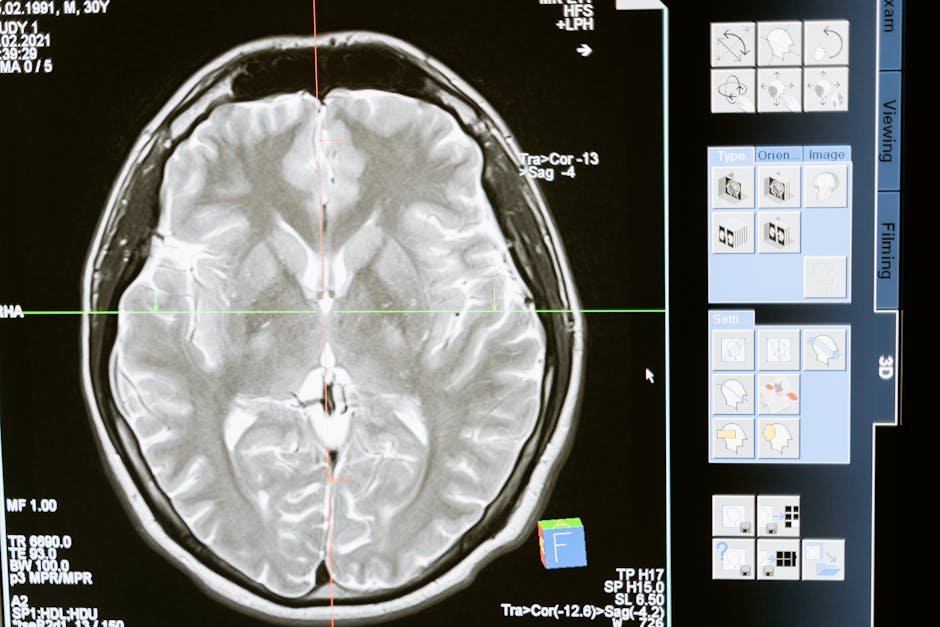

Companies use all sorts of cool brain tech—like fMRI, EEG, eye-tracking, heart rate, and even skin sensors—to get around your conscious thoughts. These tools instantly show what your brain is really doing, what catches your eye, and how you feel emotionally. This gives marketers insights into those gut feelings that sometimes totally go against what people say they want.